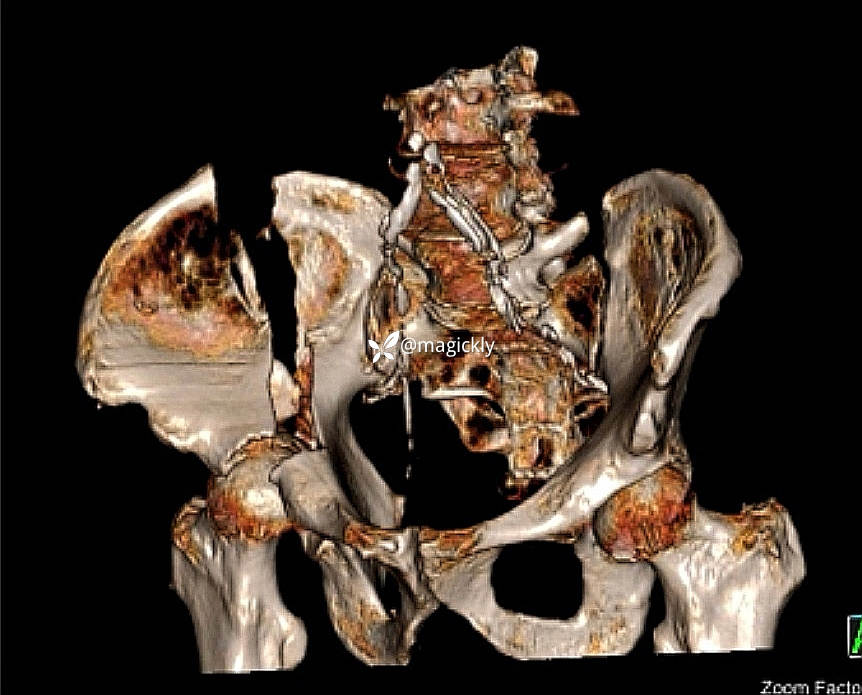

【患者信息】:男患,老年。

【主诉】:重物咋伤后右侧髋部疼痛、活动受限。

【检查】:局部体征明确,影像学结果如下

【临床诊断】:髋臼骨折(后上壁)